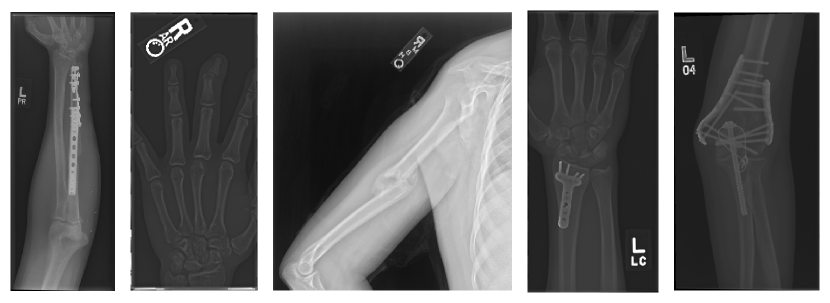

A more meaningful strategy involves modeling the distribution of normal samples and detecting any abnormal samples as those not falling on normal samples’ distribution. This general approach copes with the challenges of determining the appropriate distribution for normal data. Indeed, there is no need to label all possible anomalies, and the normal distribution can be modeled with no or few labeled samples. Therefore, unsupervised and semi-supervised approaches are usually preferred, allowing a notable reduction of annotations and time spent on radiologists’ reports. Some examples of abnormal X-rays are presented in Fig. 1.

We evaluate the proposed method on the Stanford Musculoskeletal Radiograph (MURA) dataset [5] composed of around 40,000 upper limb X-ray scans annotated by radiologists as either normal or abnormal. Each bone X-ray is a grayscale image with 512 pixels major axis. The images are first pre-processed offline to extract the X-ray image carrier and generate a body part segmentation mask. Examples of X-ray image carrier detection and segmentation masks are presented in Fig. 3 and Fig. 4, respectively. Upon image loading, further online processing is applied to transform the data using heavy augmentations, including random cropping and random color distortions during the pre-training step. Please refer to Fig. 5 for online processing details. The dataset is then split into train, validation, and test sets. Since there are multiple images of the same body part per patient, the dataset is split at the level of the patient’s body part: all images of a body part of a given patient are placed in the same set. This study focuses on semi-supervised training, which implies that we have access mainly to unknown samples and only a few labeled ones. We simulated such a settings with our splitting strategy. In total, we end up with 19,037 training images (95% of normal samples, with 5% abnormal samples), 9,910 validation images, and 10,005 test images. A visual summary of the splitting strategy is provided in Fig. 6.